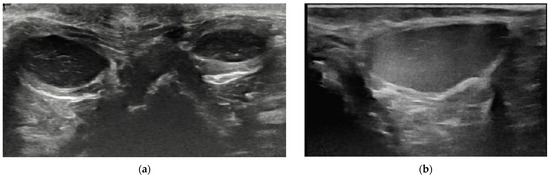

3.2. Content of Anal Sacs

3.3. Size and Shape of Anal Sacs

3.4. Wall of Anal Sacs